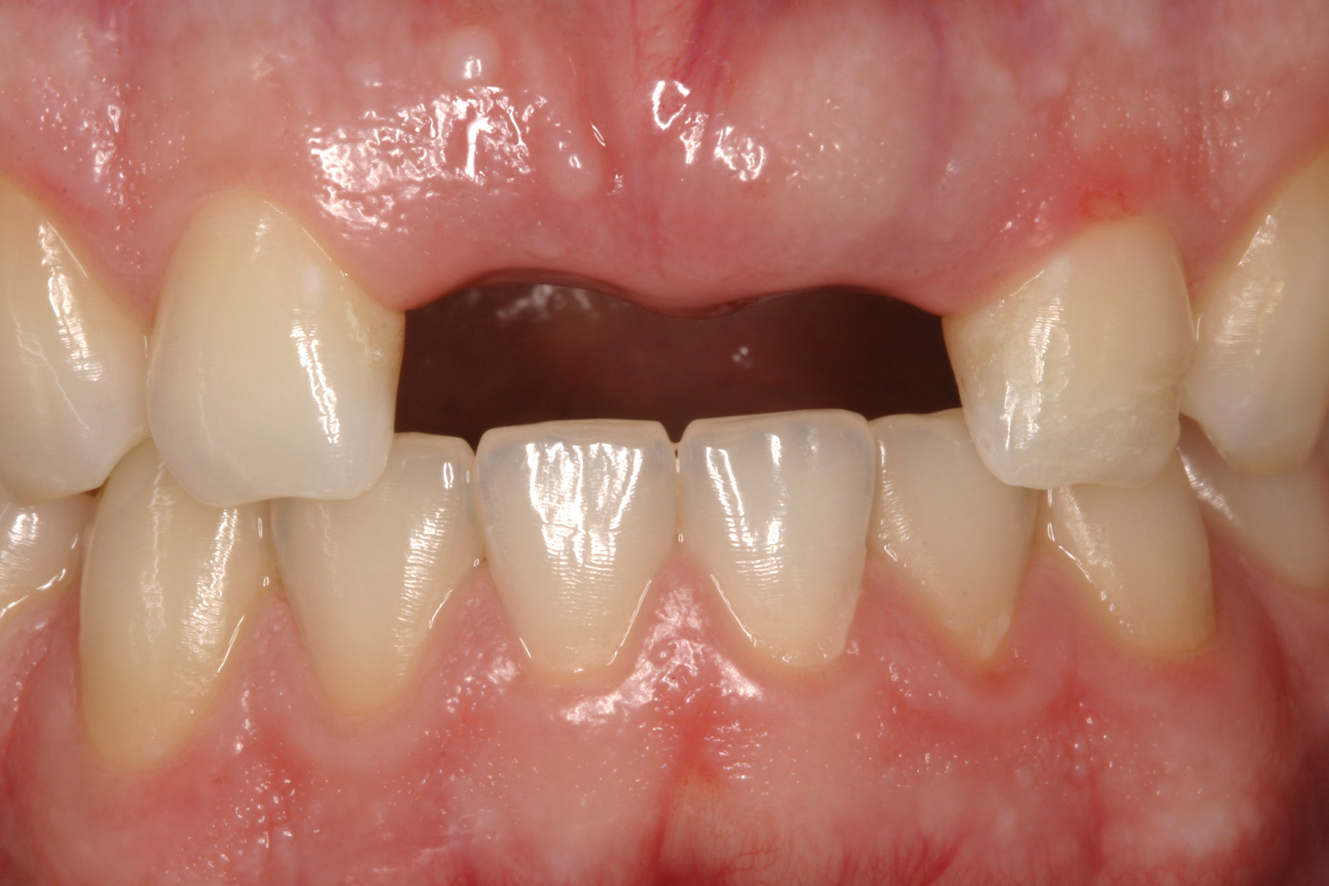

Fig 14. Age 14. Facial view of tooth No. 8 about 2.5 mm in infraocclusion.

Figure 14

The patient returned 4.5 years later, at age 14, for evaluation of his right central incisor. The tooth was now approximately 2.5 mm in infraocclusion (Figure 14). He was asymptomatic, with neither tooth No. 8 nor No. 9 tender to percussion or palpation. No. 9 had normal mobility and the PDL appeared intact radiographically. The radiograph showed No. 8 to have extensive replacement resorption of the root. Gutta-percha was exposed from the mesial CEJ around the apex and down the distal aspect of the root, leaving a sliver of coronal root about 4 mm in length attached to the distal CEJ (Figure 15).

Determining the most appropriate time to decoronate an ankylosed tooth has been discussed in the literature.24-26 Decoronation should take place near the start of adolescent rapid growth when a tooth is approximately one-eighth to one-fourth of the crown height of an adjacent homologous tooth or about 2 mm to 3 mm in infraocclusion. Decoronation at that level of infraocclusion should mitigate the development of a severe alveolar ridge defect.